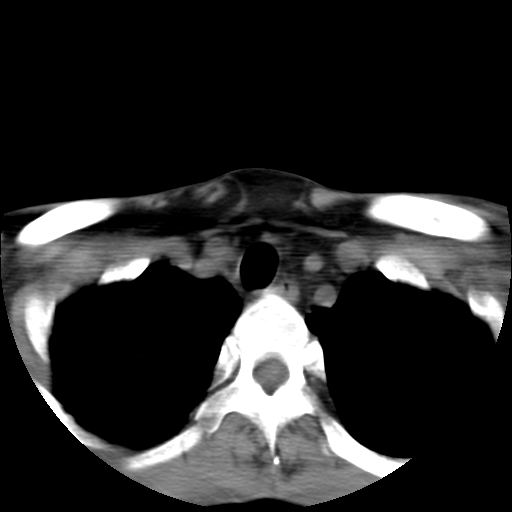

标题: CT24019:男,45岁,发现颈部肿物5个月。 [打印本页]

男,45岁,发现颈部肿物5个月,彩超示:双侧颈部及下颌部软组织增厚。

考虑双侧颈项部良性对称性脂肪增多症。